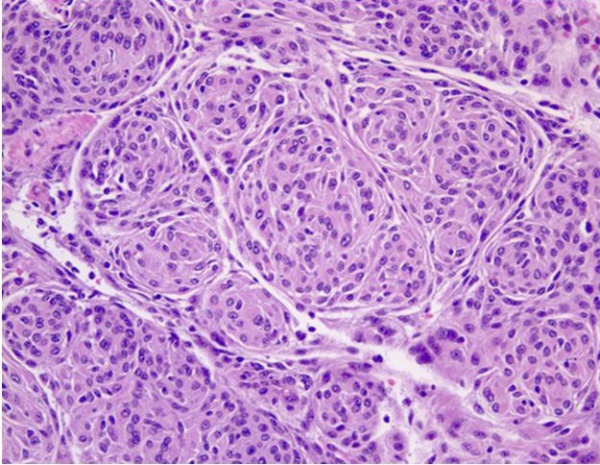

General Pathology and Classification

There is substantial pathologic variation in the appearance of sphenoid wing meningioma specimens. There are many variants encountered including secretory, microcystic, clear cell, lymphoplasmocyte rich, chordoid, atypical, malignant, papillary and anaplastic variants.[7][8] In general, the typical pathologic features that characterize most meningiomas are whorls of meningothelial cells composed of epithelioid type cells with eosinophilic cytoplasm and ovoid nuclei with or without vacuoles or pseudo-inclusions. Meningiomas may contain calcium deposition in the center of the whorls of cells called psammoma bodies. Figures 1 and 2 represent typical examples of histopathologic specimens of meningiomas.[7][8][2]